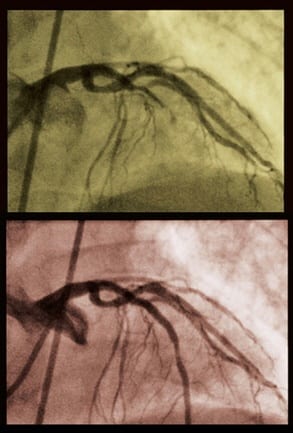

Angioplasty

– PTCA

– A catheter with a deflated balloon on the tip is inserted through the artery in the groin or arm. X-ray is used to guide the catheter up into the heart.

– The catheter is threaded up into the narrowed artery of the heart. The balloon is then inflated and deflated several times to squeeze the plaque deposit against the wall of the artery.